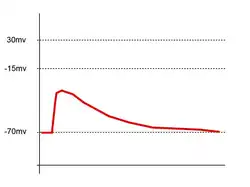

La liberación de neurotransmisores es iniciada por la llegada de un impulso nervioso (o potencial de acción), y se produce mediante un proceso muy rápido de secreción celular: en el terminal nervioso presináptico, las vesículas que contienen los neurotransmisores permanecen ancladas y preparadas junto a la membrana sináptica. Cuando llega un potencial de acción se produce una entrada de iones calcio a través de los canales de calcio dependientes de voltaje. Los iones de calcio inician una cascada de reacciones que terminan haciendo que las membranas vesiculares se fusionen con la membrana presináptica y liberando su contenido a la hendidura sináptica.

Los receptores del lado opuesto de la hendidura genéricamente densidad post-sináptica el "aparato espinal" (SA), vesículas recubiertas y un citoesqueleto complejo compuesto por filamentos delgados y partículas densas o red postsináptica), se unen a los neurotransmisores y fuerzan la apertura de los canales iónicos de la membrana postsináptica, haciendo que los iones fluyan hacia o desde el interior, cambiando el potencial de membrana local.

El resultado es excitatorio en caso de flujos de despolarización, o inhibitorio en caso de flujos de hiperpolarización. El que una sinapsis sea excitatoria o inhibitoria depende del tipo o tipos de iones que se canalizan en los flujos postsinápticos, que a su vez es función del tipo de receptores y neurotransmisores que intervienen en esa sinapsis.

Fuerza sináptica

La fuerza de una sinapsis viene dada por el cambio del potencial de membrana que ocurre cuando se activan los receptores de neurotransmisores post-sinápticos. Este cambio de voltaje se denomina potencial postsináptico, y es resultado directo de los flujos iónicos a través de los canales receptores post-sinápticos. Los cambios en la fuerza sináptica pueden ser a corto plazo y sin cambios permanentes en las estructuras neuronales, con una duración de segundos o minutos, o de larga duración (potenciación a largo plazo o LTP), en que la activación continuada o repetida de la sinapsis implica que los segundos mensajeros inducen la síntesis proteica en el núcleo de la neurona, alterando la estructura de la propia neurona. El aprendizaje y la memoria podrían ser resultado de cambios a largo plazo en la fuerza sináptica, mediante un mecanismo de plasticidad sináptica.

Integración de señales sinápticas

Generalmente, si una sinapsis excitatoria es fuerte, un potencial de acción en la neurona pre-sináptica iniciará otro potencial en la célula post-sináptica. En una sinapsis débil, el potencial excitatorio post-sináptico ("PEPS") no alcanzará el umbral para la iniciación del potencial de acción. En el cerebro, cada neurona mantiene conexiones o sinapsis con muchas otras, pudiendo recibir cada una de ellas múltiples señales. Cuando se disparan potenciales de acción simultáneamente en varias neuronas que se unen en sinapsis débiles a otra neurona, pueden forzar el inicio de un impulso en esa célula a pesar de que las sinapsis son débiles.